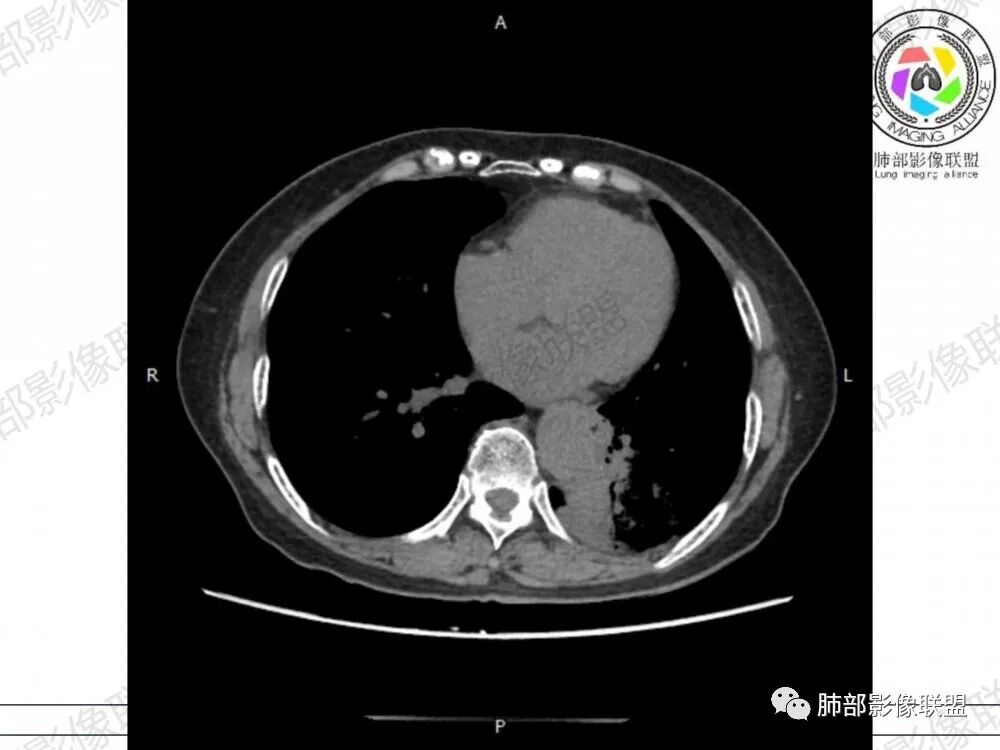

胸CT:左下叶胸膜下大片斑片影,长轴沿胸膜分布,实变、GGO混杂,磨玻璃边界清晰,粘液密度,小叶内间隔增厚,支气管进入后堵塞(枯枝),增强轻中度强化,血管造影征。常规考虑:肺腺癌?淋巴瘤?鉴别不典型病原体感染。

2、影像表现:无肺气肿背景,病变定位于左肺下叶背内侧基底段,病灶呈不规则团块影,靠近胸膜侧,其内密度不均匀,内见空洞、实变及磨玻璃影,磨玻璃影呈碎石路征,边界清楚,实性肿块边界膨隆,其内见空洞。空洞周围比较实。病灶较大的支气管通畅,细小的支气管成“枯枝征”。无胸膜增厚及胸膜腔积液,增强扫描呈中度强化,见血管造影征。

2、典型的粘液腺癌,收缩力很弱,肺泡壁断裂常有,张力存在,早期较少出现张力表现,破坏力偏弱,支气管与肺血管大多保留,所以增强病灶内见强化血管影(血池),也是粘液腺癌另一个特点。

3、 由于粘液重力作用,粘液腺癌易发生于下肺胸膜下,由于小叶间隔阻挡,胸膜侵犯少,通常是胸膜与周围肺组织的模糊增厚,粘液腺癌的胸膜侧较宽,但胸水少见也是诊断特点之一。